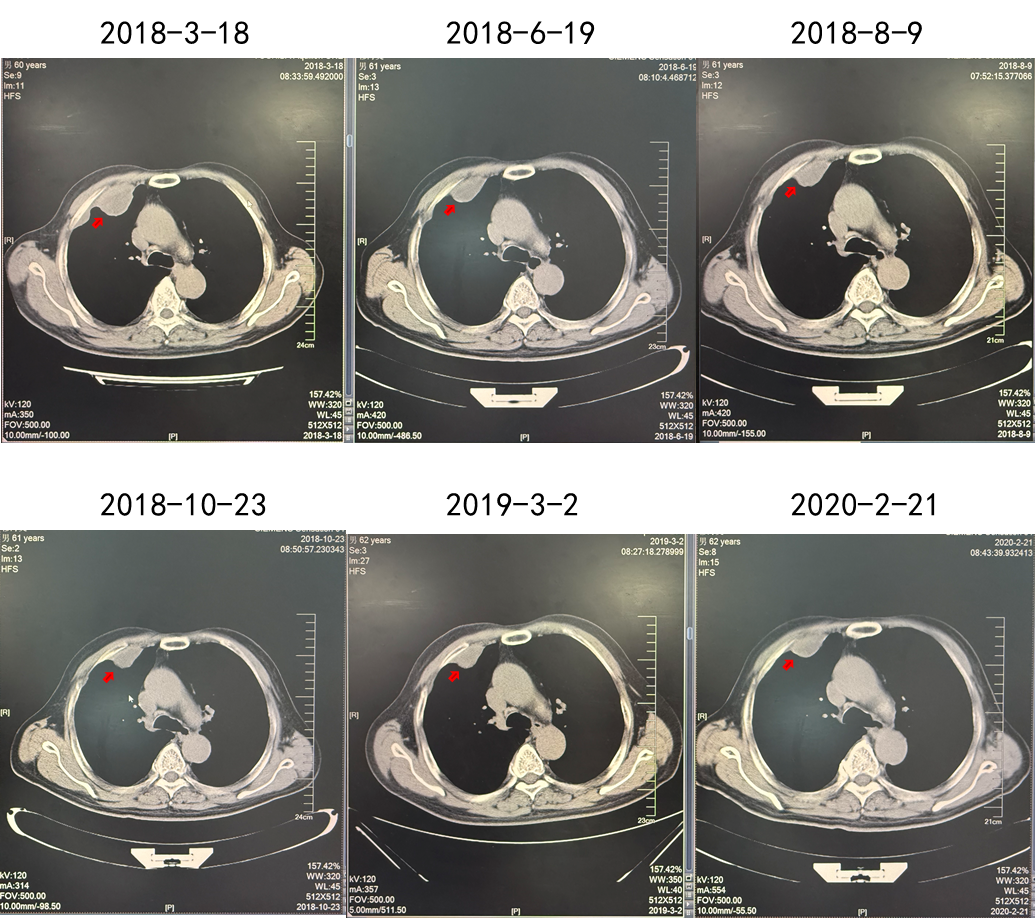

第二阶段:靶向治疗同步放疗

2018.03.22舒尼替尼50 mg QD。肋骨肿瘤注射唑来膦酸3周1次(共3次),同步放疗3 Gy(共10次)。

2018.03.24由于患者出现不良反应,调整剂量为37.5 mg QD。

疗效:肋骨病灶疾病稳定(2年),肺部病灶部分缓解(2年)。

(舒尼替尼单药联合放疗,肋骨病灶实现SD)

(舒尼替尼单药联合放疗,肺转移病灶实现PR)